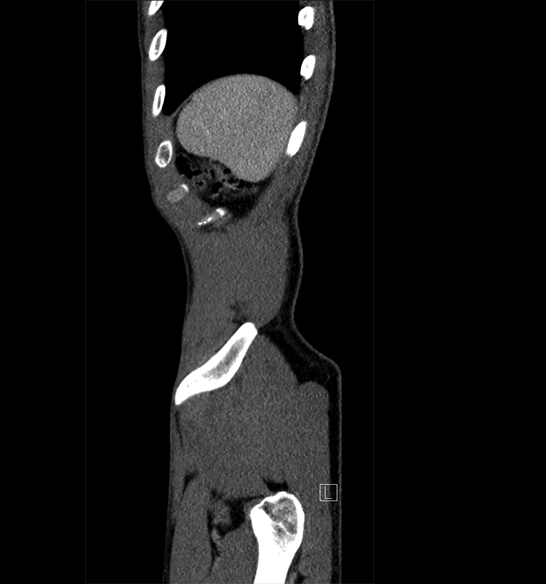

Body

Covers abdominal CT anatomy.